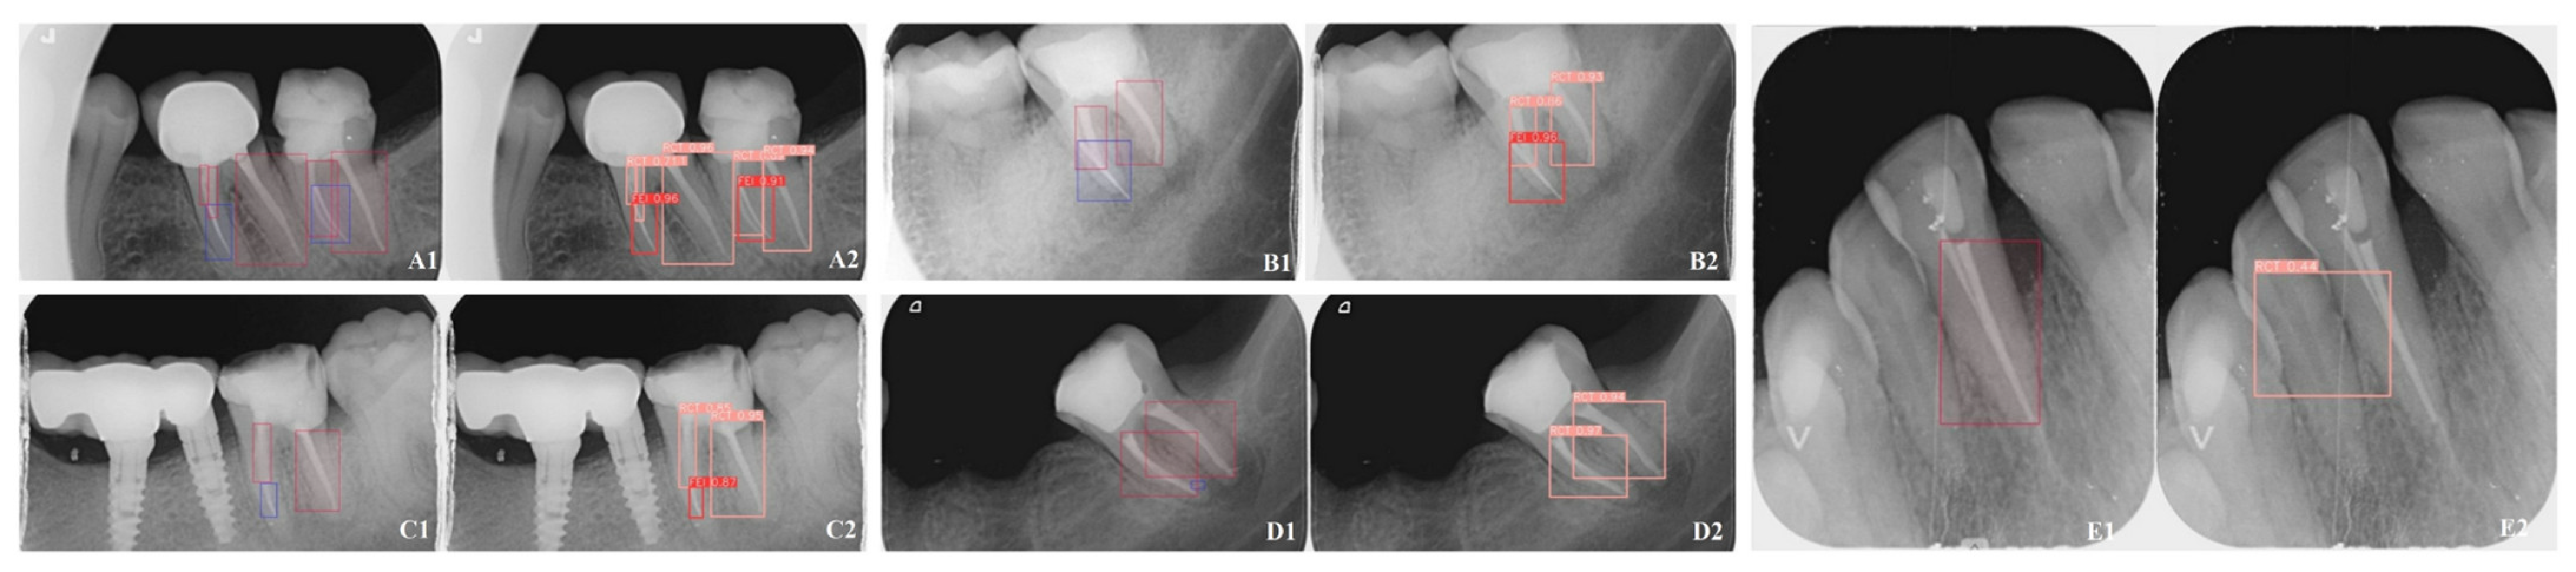

Figure 1. Representative examples of Mask R-CNN’s performance on periapical radiographs (PAs) for detecting fractured endodontic instruments (FEI) and root canal treatments (RCT). The bounding boxes and associated confidence scores highlight the model’s ability to accurately identify and localize objects. Panels (A1E1) represent the ground truth annotations marked with blue boxes for FEI and red boxes for RCT, while panels (A2E2) depict the segmentations generated by the Mask R-CNN model, where FEI is marked with red boxes and RCT with pink boxes.